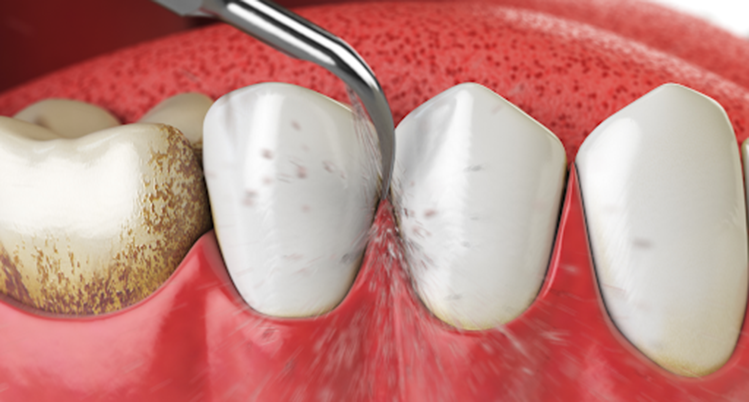

2. スケーリング(歯石除去)

歯科医院で行うクリーニングの中に含まれるもので、専用の機械や器具を使用して歯石を取り除きます。

歯石の表面にはざらつきがあり、プラークが溜まりやすくなるため定期的に除去しましょう。

スケーリング

スケーリングとは

専用の機械や器具を使用して歯石を取り除く処置です。スケーラーという道具を使用します。

- 手用スケーラー

(器具を使って手動で除去する方法) - 超音波スケーラー

(超音波発生させる機械を使って除去する方法) - エアスケーラー(空気の力で振動する

機械を使って除去する方法)

この3パターンがあります。

機械では沁みる場合があるため、知覚過敏が強い方や痛みに弱い方には、手用スケーラーのみで対応することもあります。

スケーリングで歯石を除去する重要性

歯石は歯垢(プラーク)が石灰化したものです。

大量の細菌が含まれていますが、歯ブラシの力では除去することができません。

特に歯周病の場合は、歯ぐきの中に歯石が入り込むため、気づかずに放置してしまう方も少なくないのです。

歯周病を悪化させないためにも、定期的なクリーニングで歯石の除去をおすすめします。